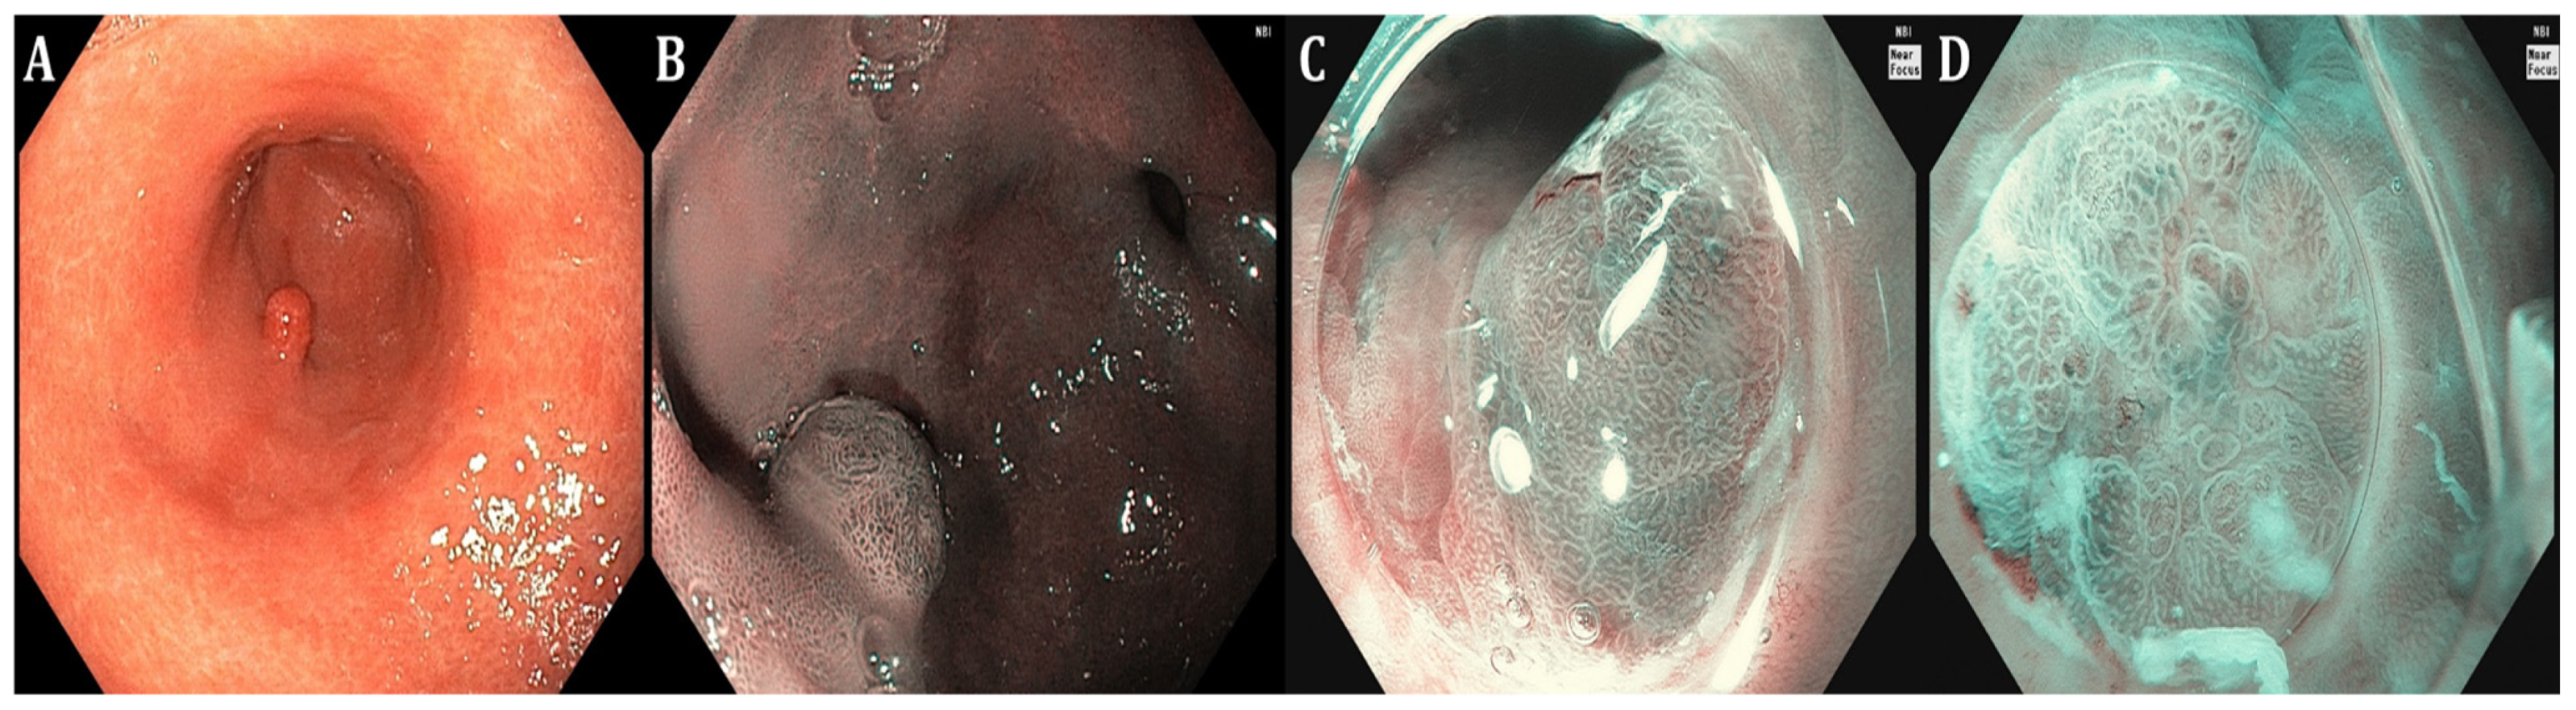

| GIM endoscopic findings | Light-blue crest (LBC) as fine blue–white line on the crest of the epithelial surface, white opaque substance (lipid droplets) obscuring the subepithelial capillaries, multiple pale, elevated patches | Elevated greyish white patches surrounded by pale and normal-color gastric mucosa or blotchy patchy erythema, lipid droplets termed white opaque substance (WOS), patchy reflections of blue–white located on epithelial margins termed light-blue crest | Lavender area, “Lavender color sign” (LCS); “Purple in Mist” (purple mixed with white on the epithelium, with signs of mist detected by non-magnifying LCI observation—PIM); “patchy lavender color” (patchy lavender color with a regular mucosal pattern and a clear border—PLC) |